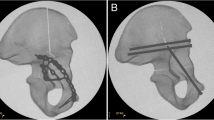

All instrumentations were performed in accordance with manufacturer recommendations and instrumentation sets. Fluoroscopy (GE FlexiView 8800; GE Healthcare, Waukesha, WI, USA) was used to confirm appropriate hardware application and fracture fixation. The osteotomy was reduced anatomically and fixed in one of five ways (Fig. 1): (1) one 10-hole anterior column 3.5-mm pelvic reconstruction buttress plate supplemented with one 8.0-mm cannulated posterior column lag screw; (2) one eight-hole posterior column 3.5-mm pelvic reconstruction buttress plate supplemented with one 8.0-mm anterior column lag screw; (3) one 8.0-mm cannulated anterior column lag screw plus one 8.0-mm cannulated posterior column lag screw; (4) one 10-hole anterior column 3.5-mm pelvic reconstruction buttress plate supplemented with an infrapectineal quadrilateral surface buttress plate; and (5) one suprapectineal posterior column/quadrilateral surface buttress plate . Nonlocking 3.5-mm cortical screws were used (length range: 26–145 mm) and all fixation was provided by Stryker Trauma (Kiel, Germany). Fixation torque for the cortex and lag screws was standardized at 3 Nm (DigiTorque screwdriver [1.0–5.0 Nm]; PB Swiss Tools, Gainesville, GA, USA).

The various fixation methods are shown: (A) a 10-hole anterior column pelvic reconstruction buttress plate with a posterior column lag screw; (B) an eight-hole posterior column pelvic reconstruction buttress plate with a posterior column lag screw; (C) a 10-hole anterior column pelvic reconstruction buttress plate supplemented with an infrapectineal quadrilateral surface buttress plate; and (D) a suprapectineal posterior column/quadrilateral surface buttress plate.